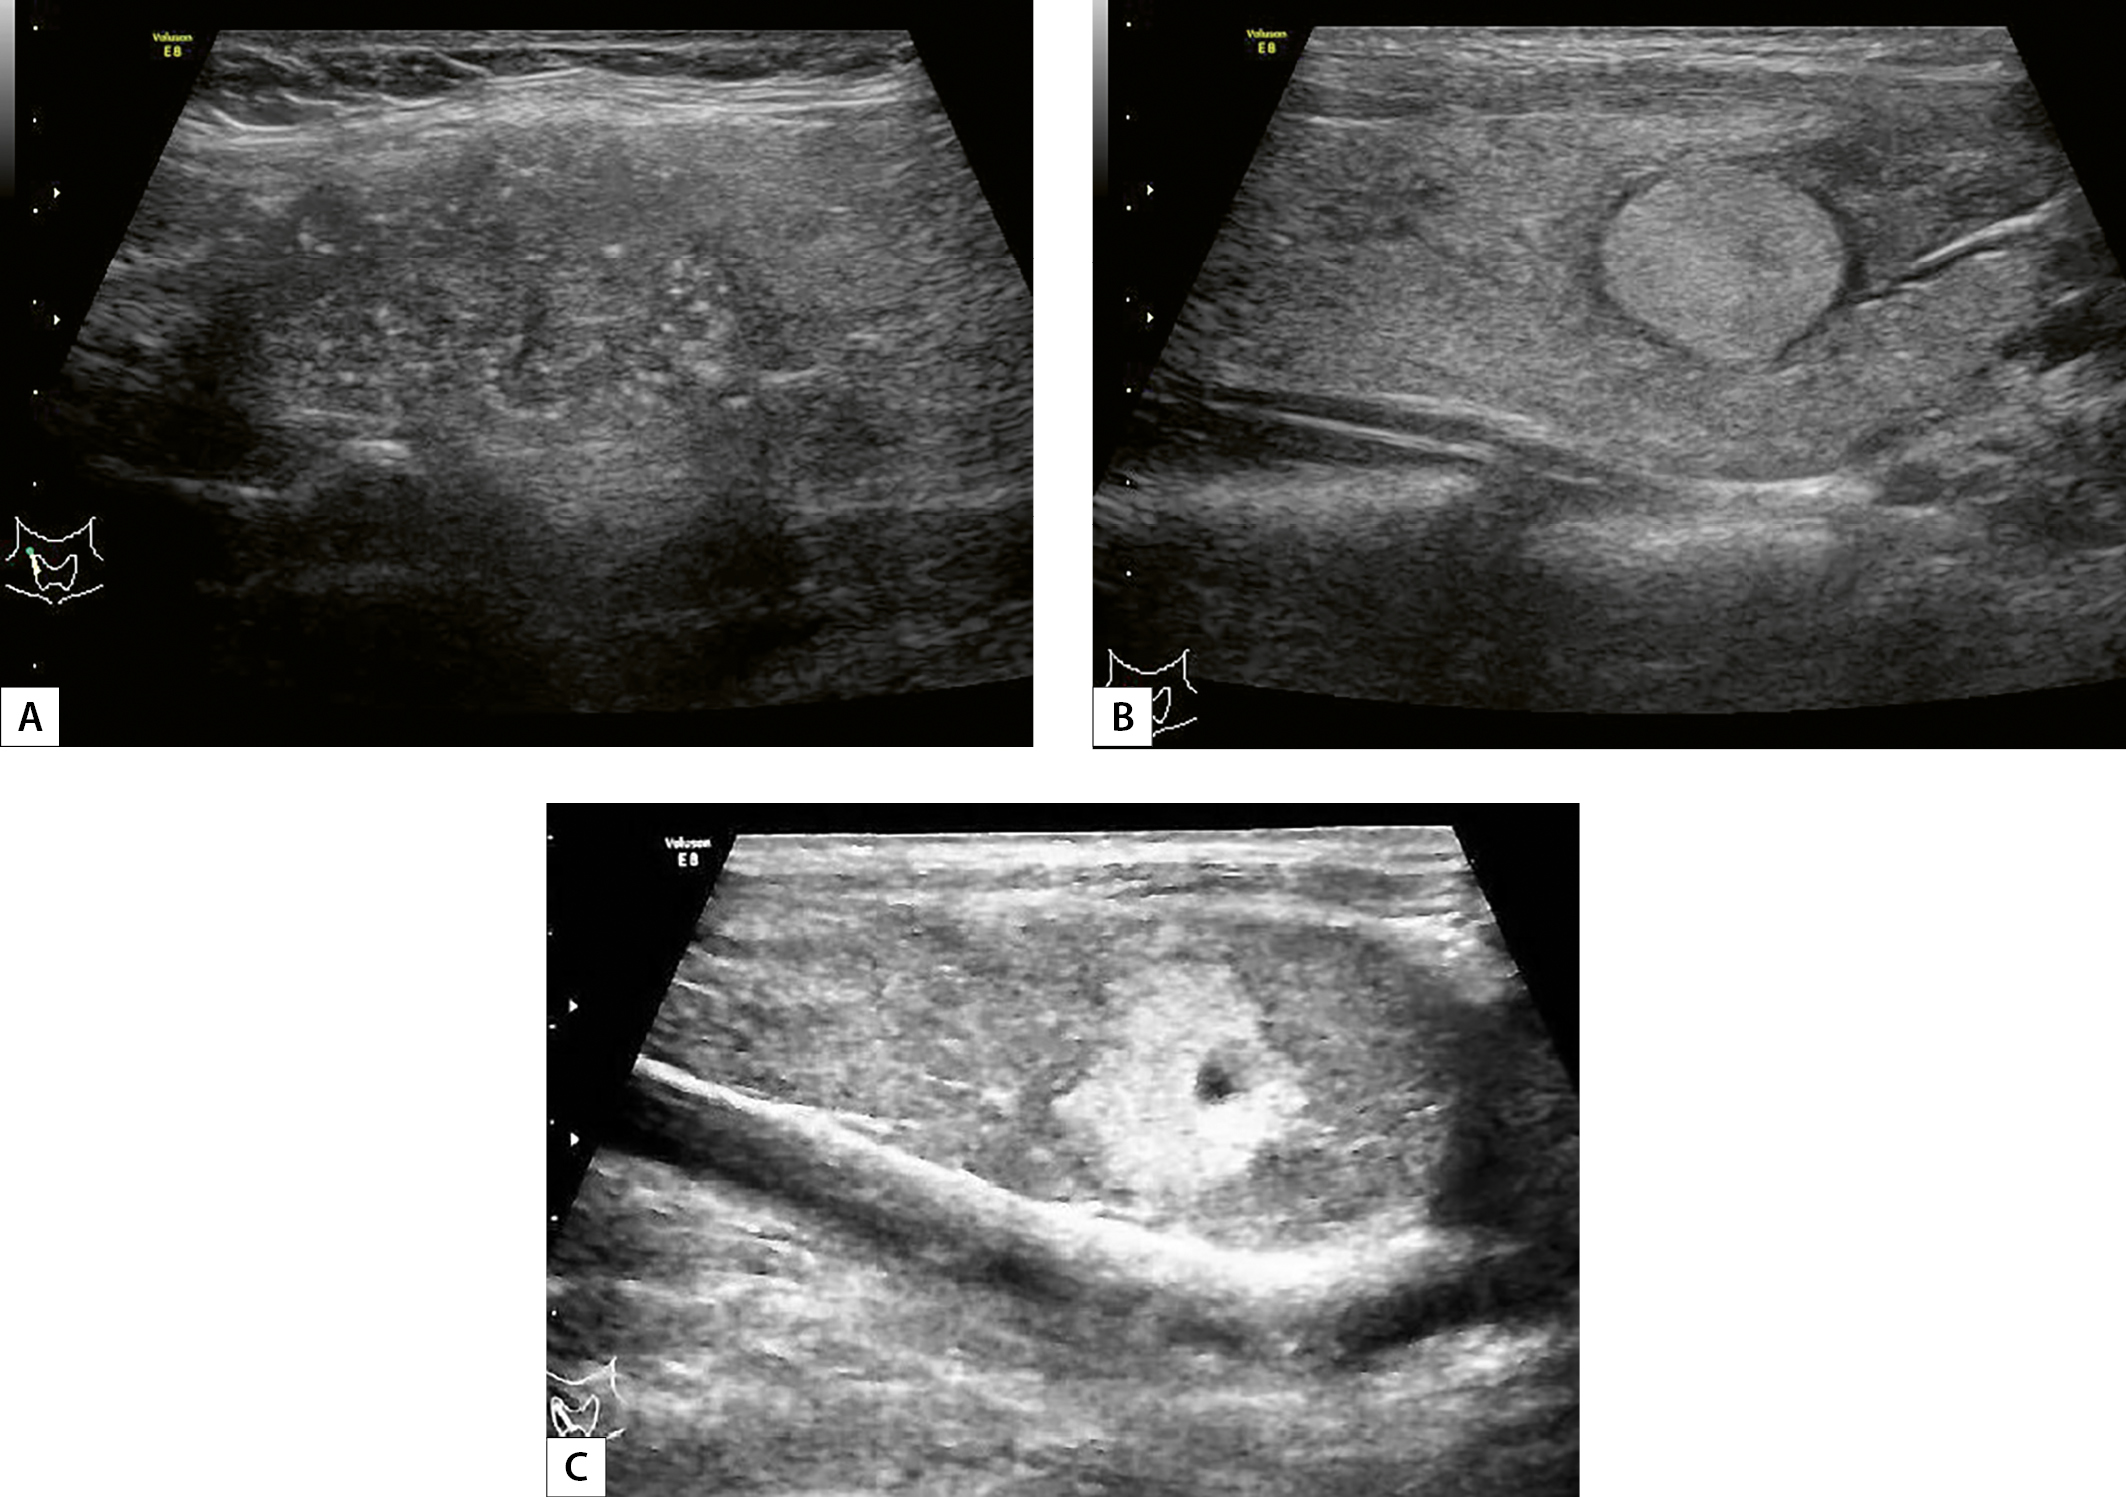

3. Рисунок 3. Эхограммы щитовидной железы: продольный срез (A–C). В верхнем полюсе правой доли — образование размерами 2,7х2,5х1,4 см с нечеткими, неровными контурами пониженной эхогенности, с микрокальцинатами, EU-TIRADS 5 (A). В н/з правой доли определяется образование диаметром 1,3 см с нечеткими контурами, средней эхогенности, с гипоэхогенным ободком (B). В н/з правой доли — очаг диаметром 1,2 см, с неровными контурами, повышенной эхогенности (C). | |